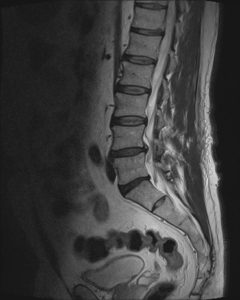

Dlatego wynik rezonansu to tylko część układanki. Najważniejsze są objawy kliniczne i badanie funkcjonalne, które pozwalają dobrać odpowiednią terapię.

„Wypadnięcie dysku” to w rzeczywistości przepuklina krążka międzykręgowego, czyli pęknięcie pierścienia włóknistego i przemieszczenie części jądra miażdżystego.

Dysk także nie „wypada”, tylko jego zawartość może przemieścić się w stronę nerwu.